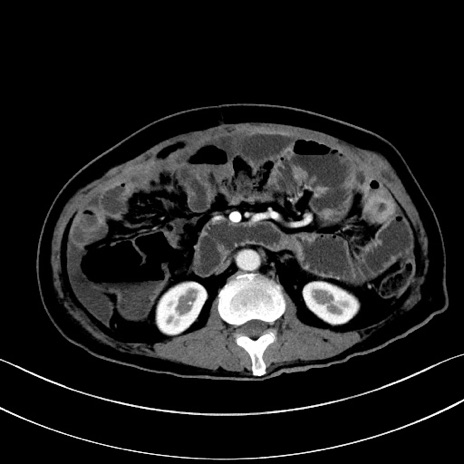

症例28(横断像)

【症例】60歳代男性

【主訴】嘔吐

【現病歴】胃癌にて胃全摘後。食思不振が悪化し、夜中に嘔吐することがある。

【既往歴】胃癌、胃全摘、脾摘、胆摘後

【データ】WBC 5900、CRP 10.56